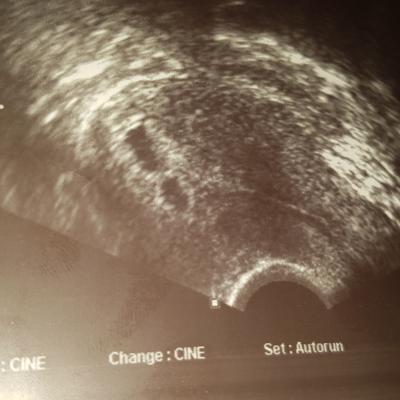

Guten morgen Mädels. Ich war gestern bei 5+2 beim Arzt und meine Ärztin sah 2 Fruchthöllen allerdings nur ein Dottersack,kann der 2 noch folgen oder ist das eher gering und er stirbt ab? Wer hatte Erfahrung? Sonst ist alles der Ssw entsprechend. Ich gehe nächste Woche Donnerstag noch mal zum Frauenarzt und bekomme den Mutterpass. Eine hier im Forum meinte sie könnte den 2 Dottersack mit Pfanthasie erarnen???? Anbei ein Foto.

Bild zu 2 Fruchthöllen 1 Dottersack - Schwanger - wer noch? Rund um die Schwangerschaft